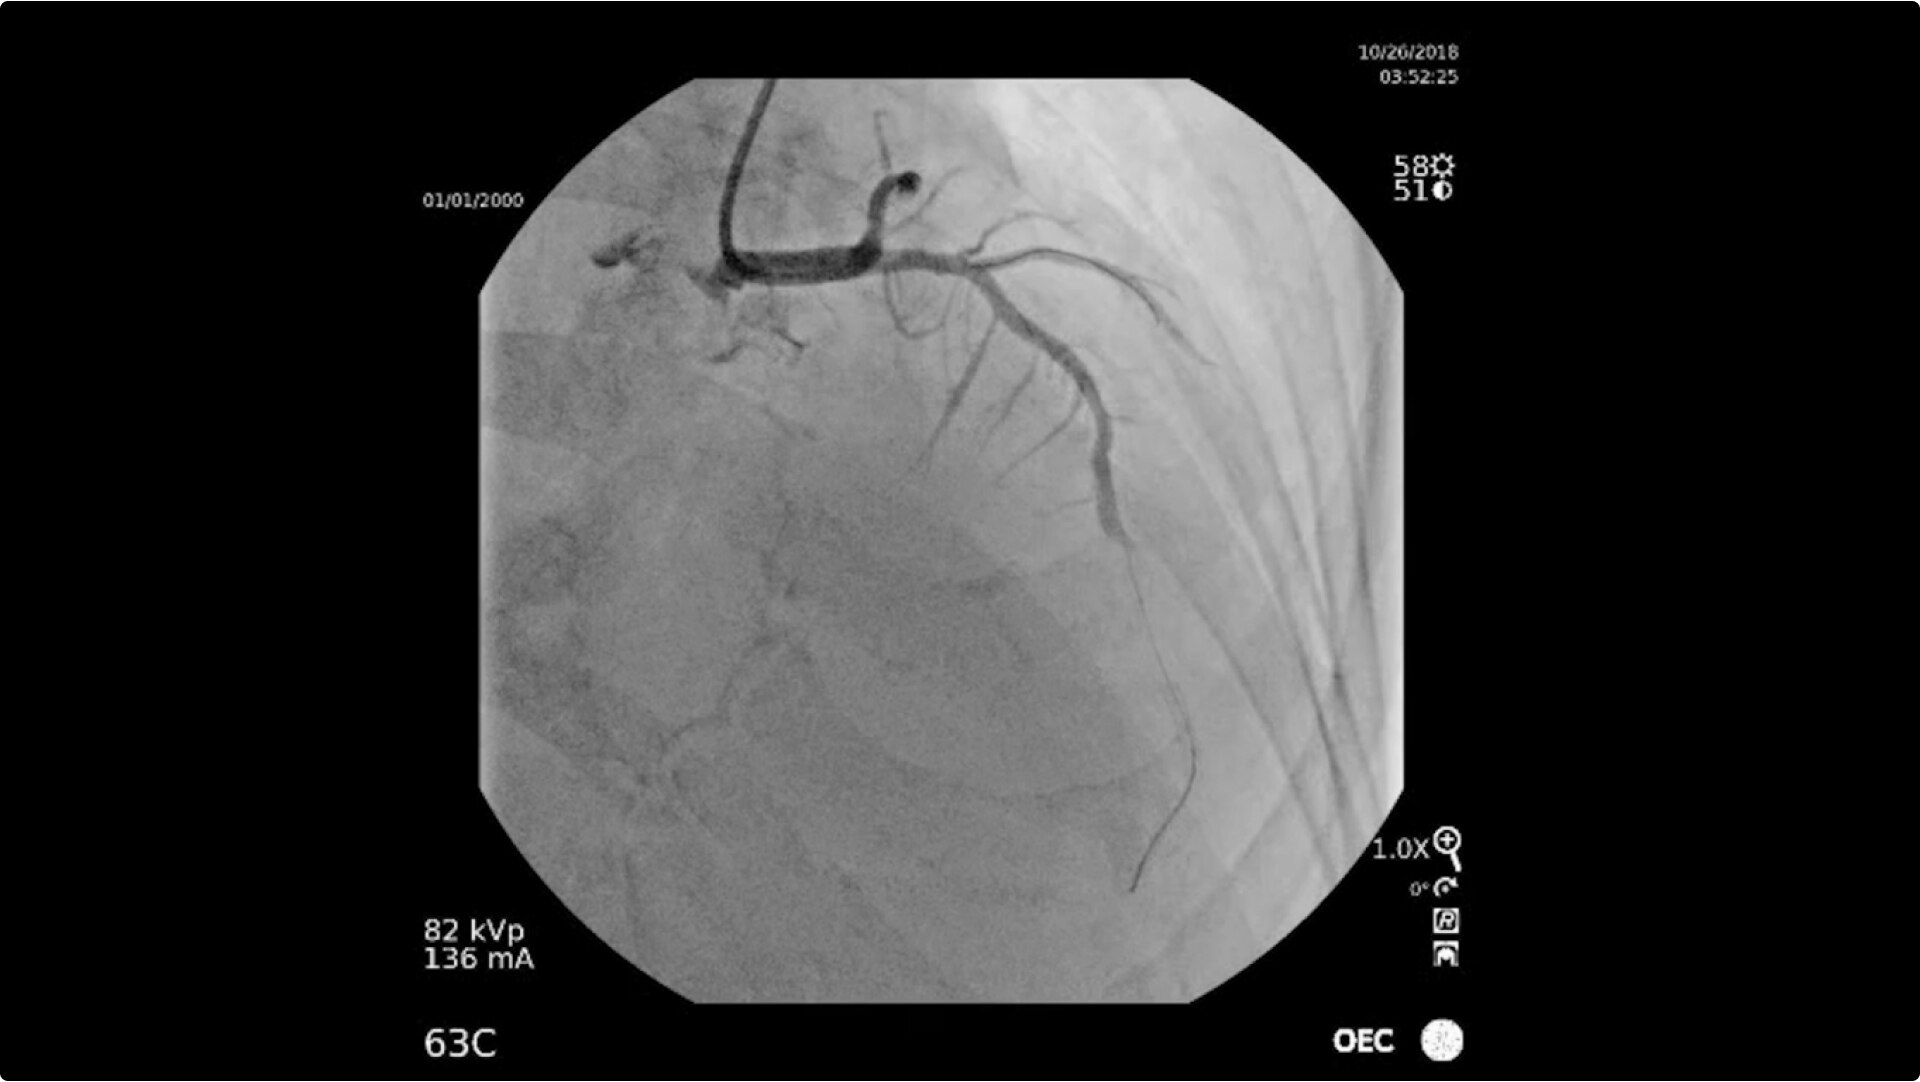

Achieve high-quality visualization necessary for complex cardiac procedures. OEC C-arms offer amazing image quality at low dose for efficient interventional imaging. Interventionalists and surgeons clearly see fine details of cardiac imaging, such as the border of the heart, leads, and small guidewires. Dynamic range management enables superb resolution, even with motion, during cardiac procedures.

See 0.014” guidewires in thoracic region or wire leads when placing biventricular pacemakers with the OEC Elite CFD flat detector, image processing, and 4K display.

Visualize moving interventional devices (catheters, stents) in vessels of the heart with the Cardiac Preset profile that automatically reduces blooming artifacts.

• Coronary artery diagnosis

• Percutaneous coronary intervention